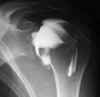

Artrografie

Een arthrografie wordt uitgevoerd om een gewrichtsholte te visualiseren. Hiervoor wordt een contrastmedium in het gewricht gespoten. Vaak wordt er eveneens lucht ingespoten. Dit om een duidelijker beeld te verkrijgen van de kraakbeenoppervlakken van de gewrichten. Na een aantal opnames op de conventionele radiologie wordt er een CT-scan gedaan om het gewricht beter nog te kunnen evalueren. Plaatselijke verdoving kan gegeven worden maar is niet de regel, denk erom dat er steeds een prik gegeven wordt, vaak is voor de punctie maar een prik nodig, met de verdoving worden het er twee.

Een arthrografie kan ook gebeuren ter voorbereiding van een MRI onderzoek. De indicaties en de de voor- en nazorg blijven indentiek.

Indicaties:

![]() | Letsels aan pezen en/of ligamenten van het gewricht |

![]() | Letsels van het gewrichtskapsel |

![]() | Ontwrichting |

![]() | Bot of kraarbeenletsels |

![]() | Gewrichtsmuizen (dit zijn kleine stukjes bot die los in het gewricht voorkomen) |